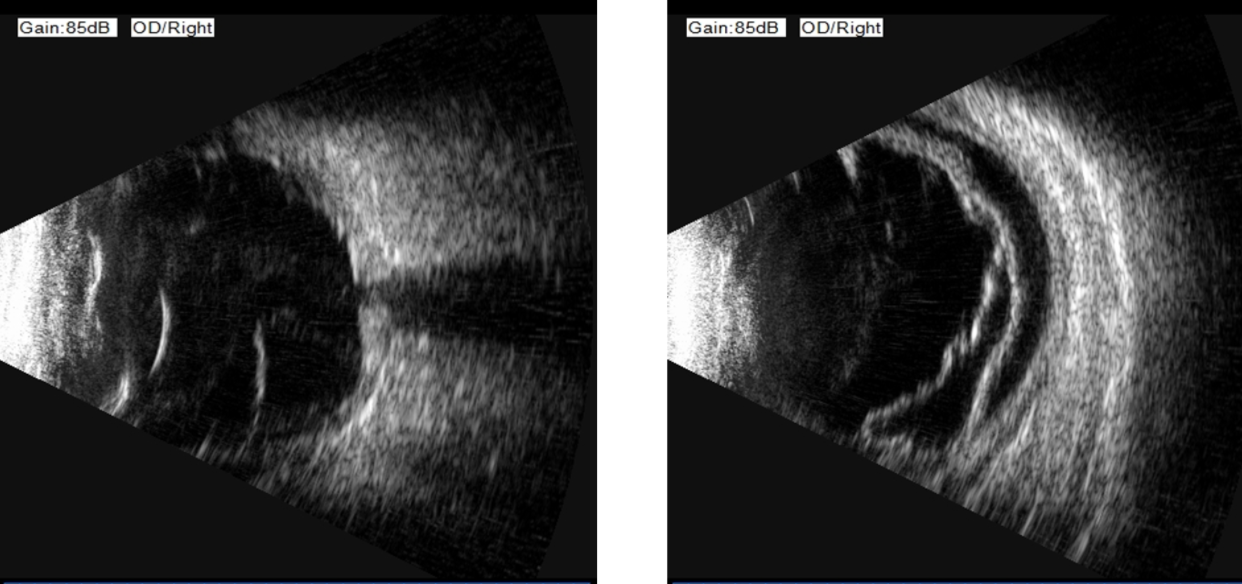

顾名思义,这个病至少包含两个表现:视网膜脱离和脉络膜脱离。1. 视网膜脱离:视网膜是眼球最内层的一层透明薄膜,相当于相机的底片。当它因为视网膜裂孔从依附的壁上“脱下来”时,就形成了孔源性视网膜脱离。患者通常会感到眼前有黑影遮挡,有闪光感、飞蚊症,脱离累及视网膜最重要的结构——黄斑中心凹时,视力会急剧下降。2. 脉络膜脱离: 脉络膜是位于视网膜和眼白(巩膜)之间的一层富含血管和色素的组织,负责为视网膜提供营养和氧气。当它因为眼压过低或炎症等原因而脱离时,眼底会表现为棕色的“鼓包样”隆起。当这两种严重的情况同时发生,就形成了脉络膜脱离型视网膜脱离。它不仅仅是“底片”脱落,更是“底片”和滋养它的“土壤”一起大面积脱离,对视力构成严重威胁。

为什么它如此凶险?与单纯的孔源性视网膜脱离相比,它具有以下几个特点,使其更为棘手:1.进展迅猛:病情发展快,往往在短时间内就发展到视网膜广泛脱离。2.炎症反应重:脉络膜富含血管,它的脱离会引发剧烈的眼内炎症,导致眼痛、眼红等症状,剧烈的炎症使治疗更加困难。3.低眼压:低眼压触发了显著的葡萄膜炎症和血管渗漏,加重脉络膜脱离,而脉络膜脱离又反过来加重低眼压,形成恶性循环,使病情迅速进展。4.治疗更复杂,预后更差: 严重的炎症和低眼压会给手术治疗带来巨大挑战,术后发生增殖性玻璃体视网膜病变的风险更高,这是导致手术失败和复发的主要原因。